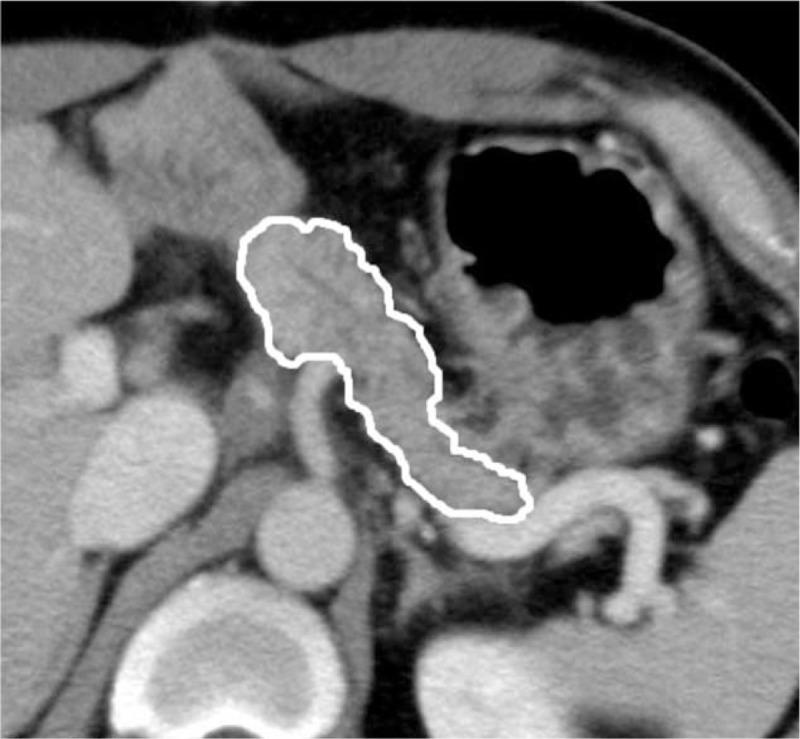

Nonalcoholic fatty liver disease (NAFLD) after pancreaticoduodenectomy (PD) has become a clinically important issue. Although pancreatic exocrine insufficiency has been reported to be a main cause of NAFLD after PD, a clinically practical examination to assess the pancreatic exocrine function has not been established. The aim of this study was to evaluate risk factors for NAFLD after PD with a focus on perioperative computed tomography (CT) assessments of the pancreas.A retrospective review of 245 patients followed for more than 6 months after PD was conducted. We evaluated several pancreatic CT parameters, including the pancreatic parenchymal thickness, pancreatic duct-to-parenchymal ratio, pancreatic attenuation, and remnant pancreatic volume (RPV) on pre- and/or postoperative CT around 6 months after surgery. The variables, including the pancreatic CT parameters, were compared between the groups with and without NAFLD after PD.The incidence of NAFLD after PD was 19.2%. A multivariate analysis identified 5 independent risk factors for NAFLD after PD: a female gender (odds ratio [OR] 5.66, P < 0.001), RPV < 12 mL (OR 4.73, P = 0.001), preoperative pancreatic attenuation of <30 Hounsfield units (OR 4.50, P = 0.002), dissection of the right-sided nerve plexus around the superior mesenteric artery (OR 3.02, P = 0.017) and a preoperative serum carbohydrate antigen 19-9 level of ≥70 U/mL (OR 2.58, P = 0.029).Our results showed that 2 pancreatic CT parameters, the degree of preoperative pancreatic attenuation and RPV, significantly influence the development of NAFLD after PD. Perioperative CT assessments of the pancreas may be helpful for predicting NAFLD after PD.

对245例行PD后随访超过6个月的患者进行了回顾性研究。我们评估了几个胰腺CT参数,包括手术约6个月后术前和/或术后CT上的胰腺实质厚度、胰管与实质比、胰腺衰减以及残余胰腺体积(RPV)。将包括胰腺CT参数在内的变量在PD后有和没有NAFLD的组之间进行比较。

PD后NAFLD的发生率为19.2%。多因素分析确定了PD后NAFLD的5个独立危险因素:女性(比值比[OR]5.66,P<0.001)、RPV<12 mL(OR 4.73,P=0.001)、术前胰腺衰减<30亨氏单位(OR 4.50,P=0.002)、肠系膜上动脉周围右侧神经丛的解剖(OR 3.02,P=0.017)以及术前血清糖类抗原19-9水平≥70 U/mL(OR 2.58,P=0.029)。

我们的结果表明,2个胰腺CT参数,即术前胰腺衰减程度和RPV,对PD后NAFLD的发生有显著影响。胰腺的围手术期CT评估可能有助于预测PD后NAFLD。